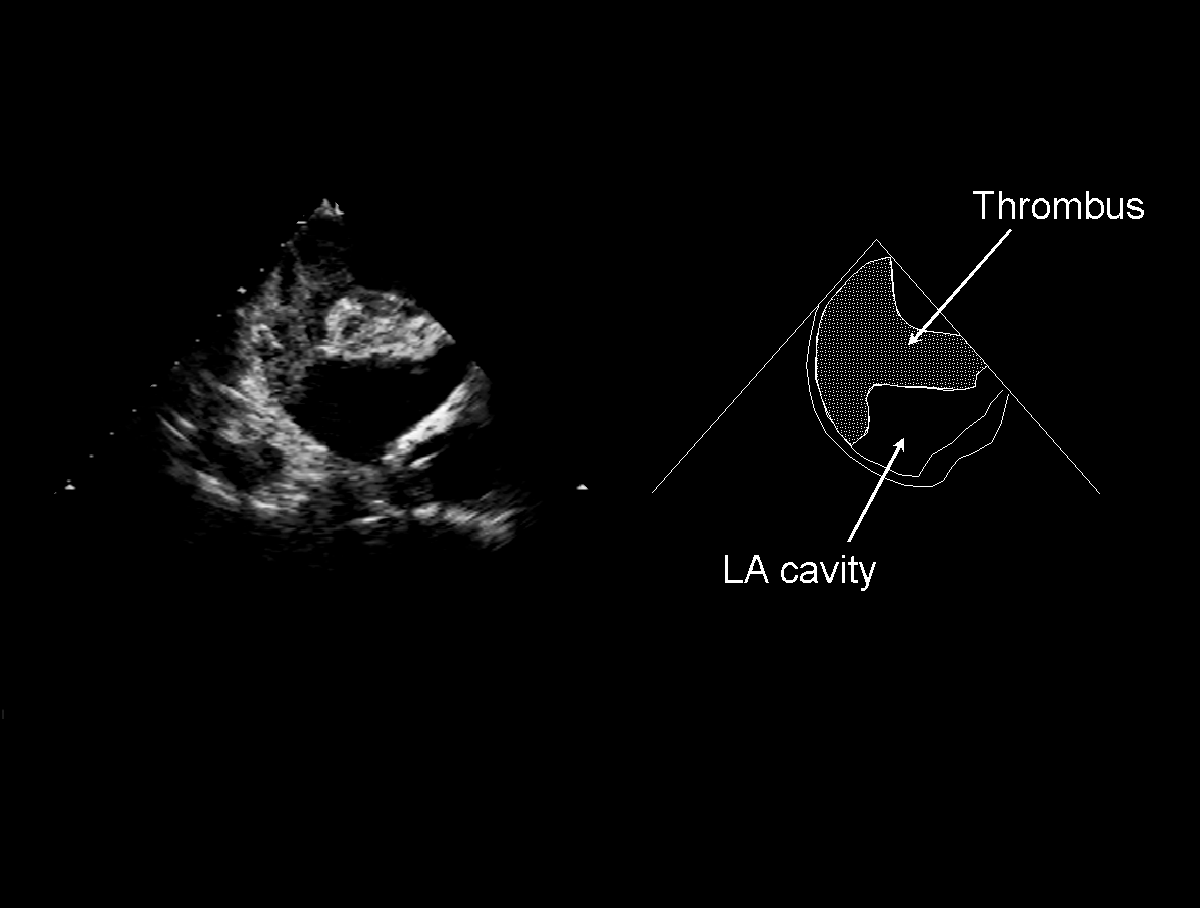

The major use of TOE is to identify clot (thrombus) in the left atrium (LA) which may be the cause of strokes.